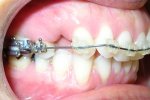

Maxillary and Mandibular midline discrepancies. Narrow, hypodeveloped

maxilla with anterior X-bite and left side posterior X-bite. Severe crowding...

CLIII skeletal & dental; Severe crowding; Posterior and anterior cross-bites; “Peg laterals”; Bimaxillary dental alveolar protrusion. Extraction...